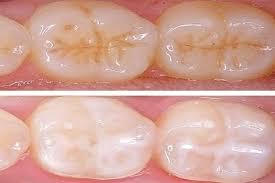

Always remember that Prevention is better than cure. Preventing dental caries is far

better than treating the cavities after getting pain or any kind of sensitivity.

Here are a few tips on how to prevent cavities:

Brushing & Flossing:

Brushing properly is the best option for how to prevent cavities. Brushing twice a day is mandatory. Many people brush incorrectly, leading to enamel loss and sensitivity. Maintaining the proper brushing technique is essential. Flossing regularly between the teeth can also help prevent interdental cavities.

Usage of Fluoride sealants:

- Early application of the fluoride sealants in the tooth surface for the kids

can prevent further dental cavities to a certain extent. - The usage of fluoridated toothpaste for kids also can prevent the cavity

formation.